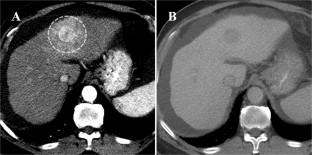

Fig. 4